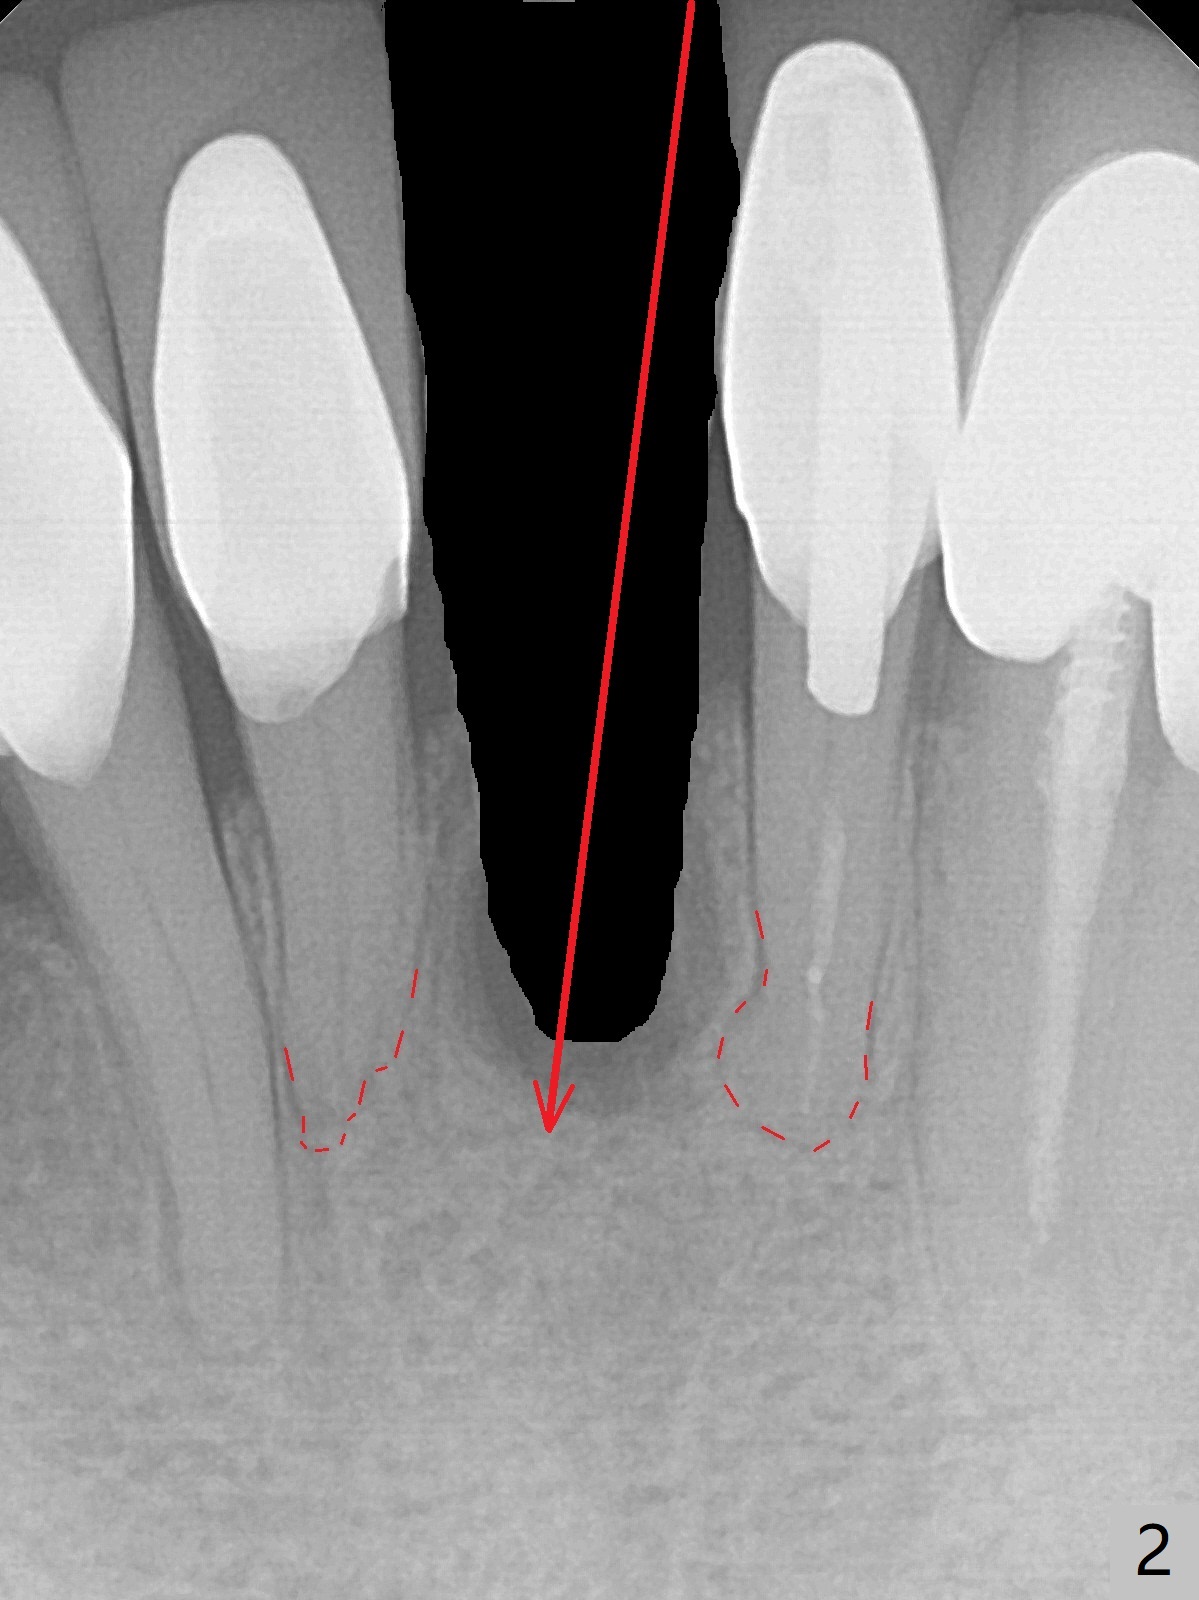

A 74-year-old man finally agrees to have the tooth #24 to be extracted for immediate implant with 3-year mobility and buccal shift (occlusal trauma or root fracture, Fig.0,1). Because of curved root tips of the neighboring teeth (Fig.1 red dashed line), the initial osteotomy will be created mesially (Fig.2 red arrow), followed by change in trajectory (Fig.3). The initial depth will be 14 mm (gingival level; ~ 12 mm bone level (easy change in trajectory and/or position). PA will be taken. The implant will be 2.5x14 mm (Fig.4).